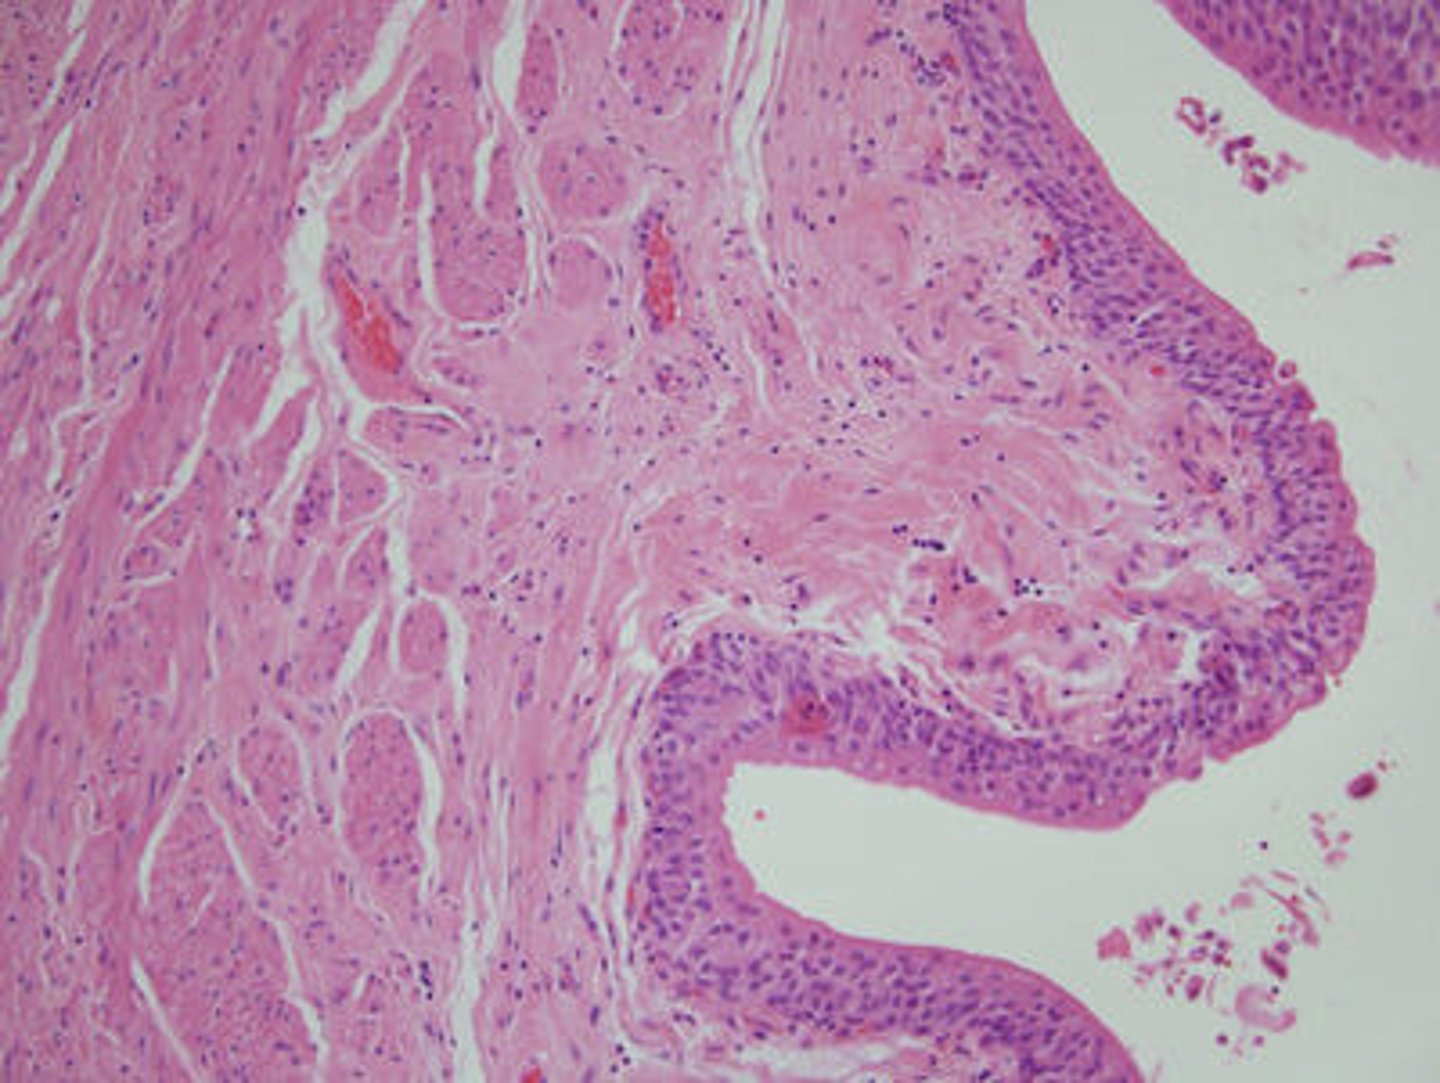

Renal corpuscle

glomerulus and bowman's capsule, simple squamous epithelial cells

glomerulus

small network of capillaries encased in the upper end of a nephron; where the filtration of blood takes place

glomerular capsule

surrounds the glomerulus

podocytes

These cells form a porous membrane (filtrate) surrounding the endothelial cells of the glomerulus

Renal tubules

small tubes in the kidney where reabsorption takes place, simple cuboidal epithelial cells